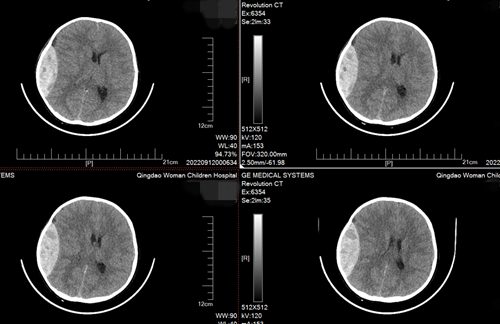

結(jié)合患兒頭部CT檢查結(jié)果,接診專家發(fā)現(xiàn)星星顱內(nèi)大量出血,出現(xiàn)腦疝,隨時會有生命危險。病情危急,救治團隊立即開放靜脈通路、補液、鎮(zhèn)靜、氣管插管維持腦灌注壓,并進行手術(shù)清除腦部積血等一系列緊急搶救措施。目前,患兒已脫離危險,痊愈出院。